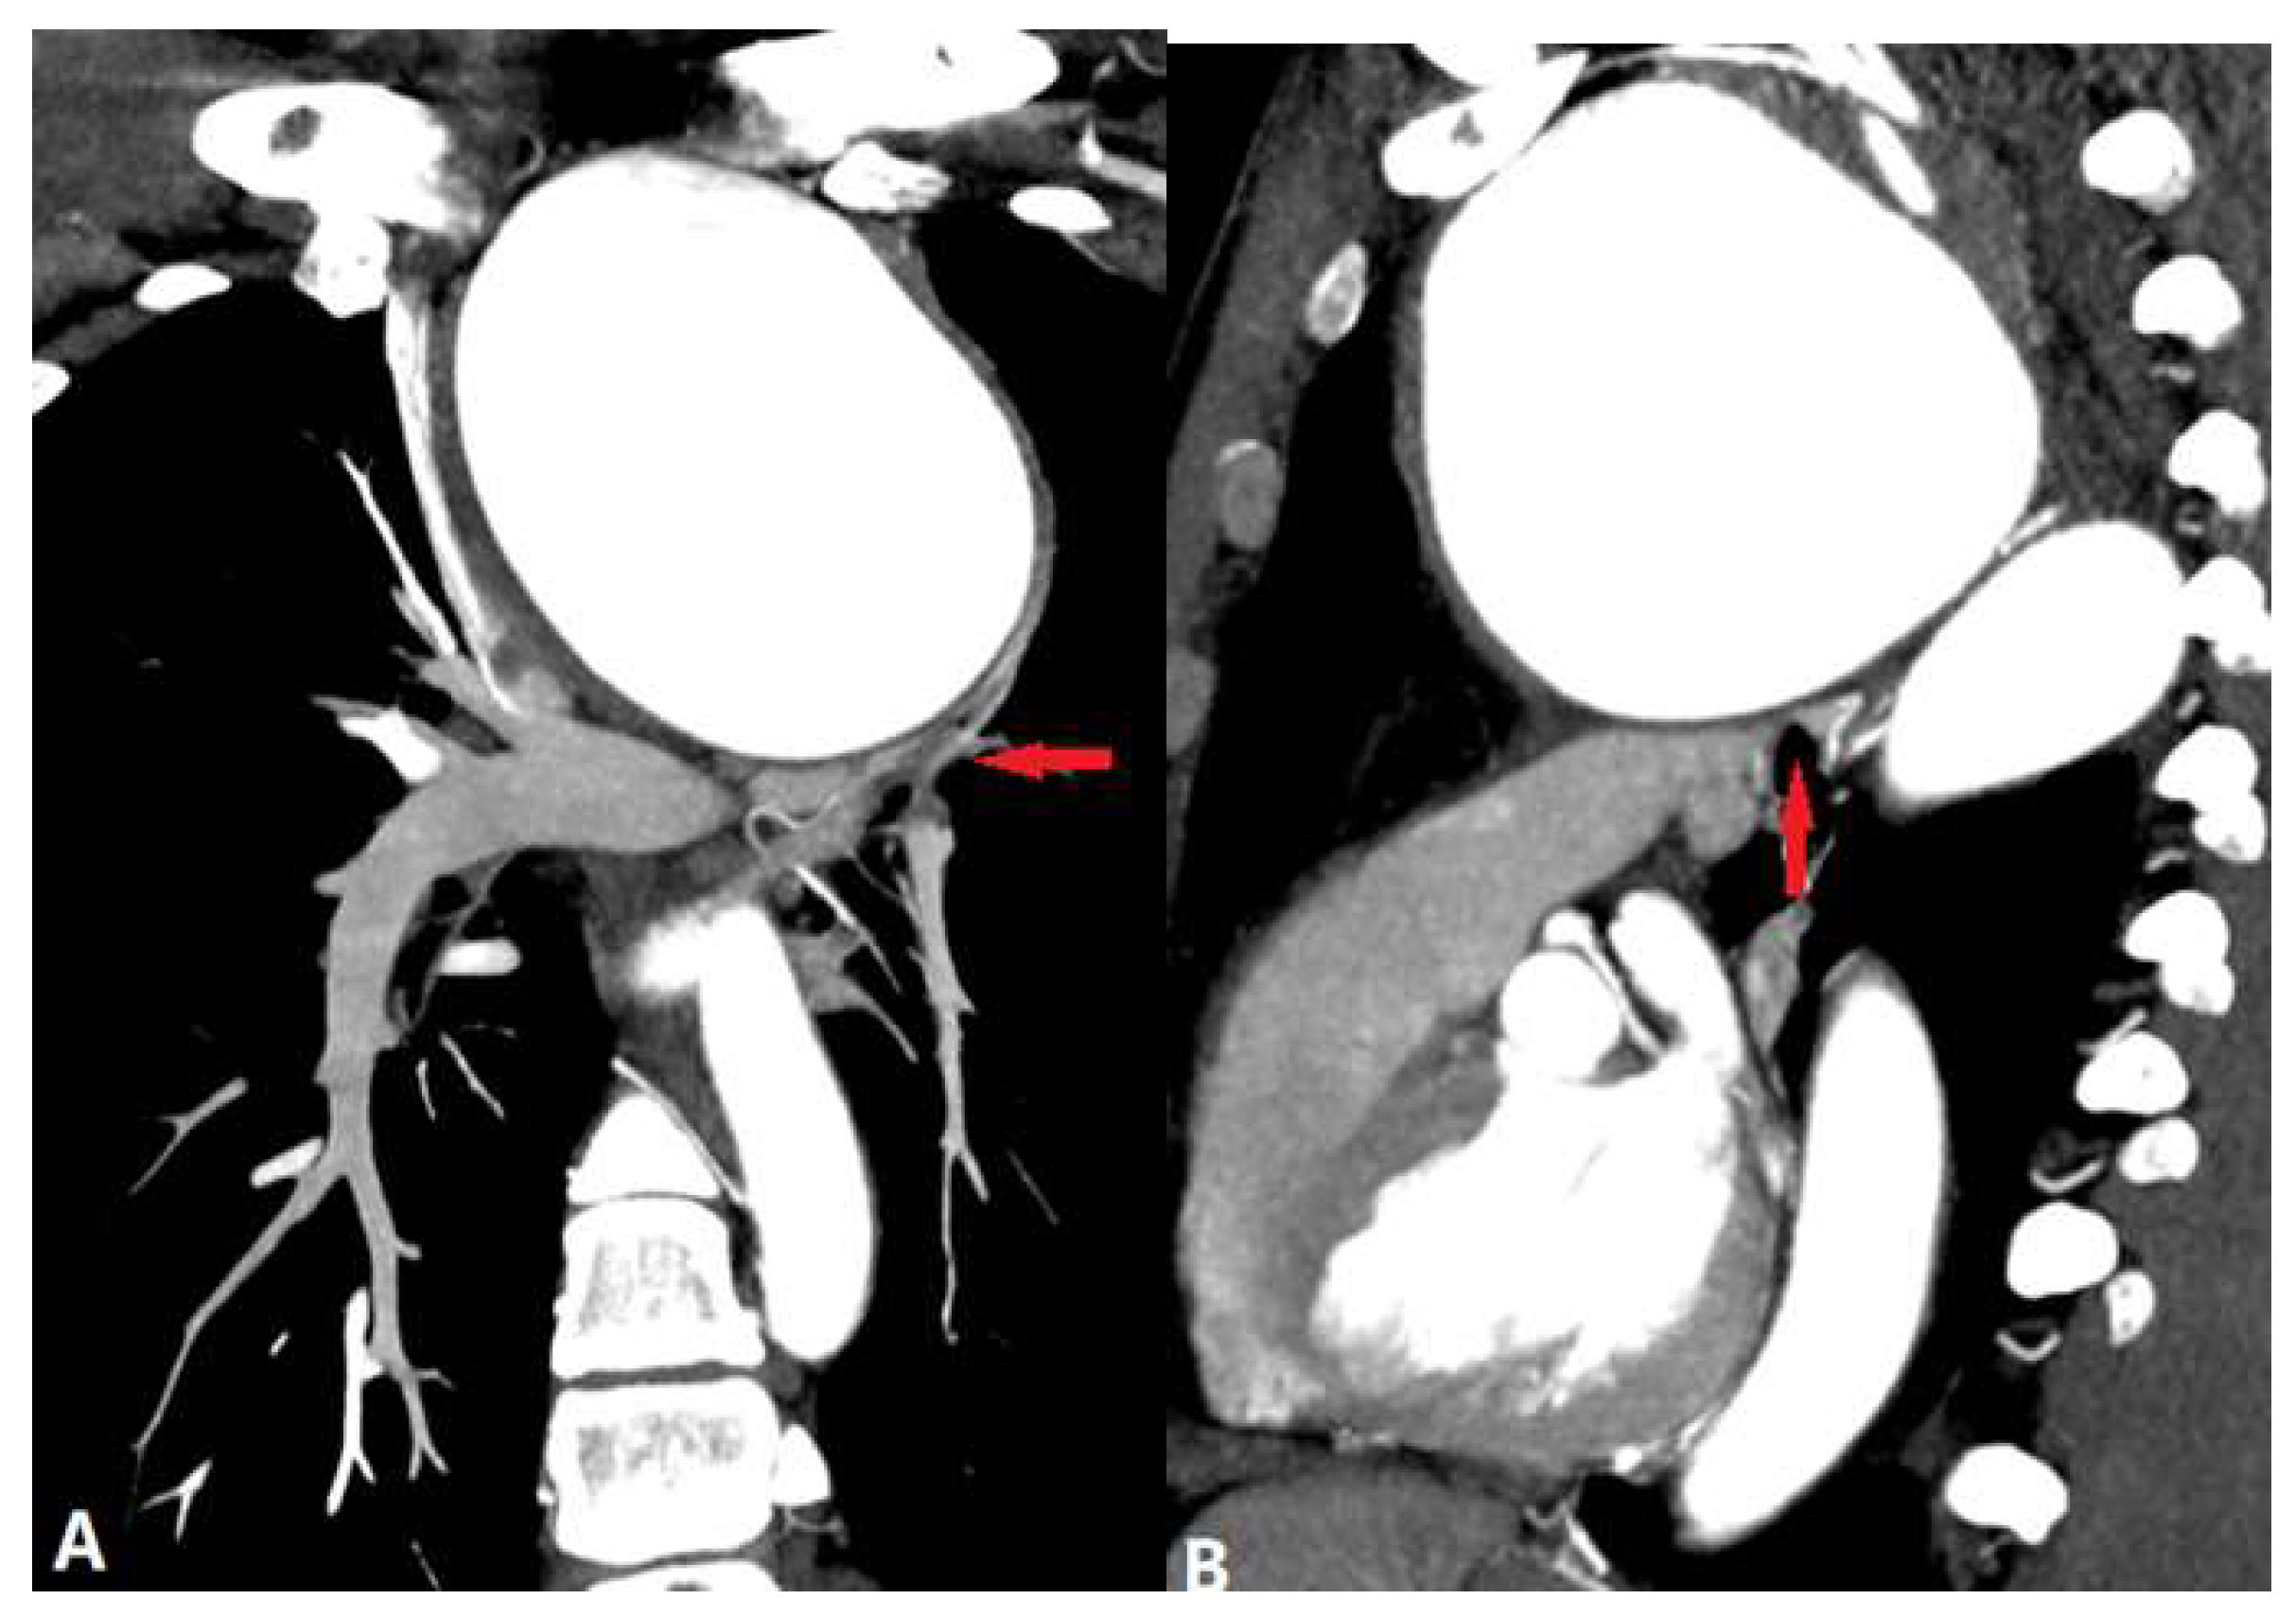

3.2. Vessel Wall Lesions

3.2.1. Vasculitis

3.2.1.1. Takayasu Arteritis (TA)

3.2.1.2. Behçet Disease (BD)

3.2.2. Arterial Dissection (AD)